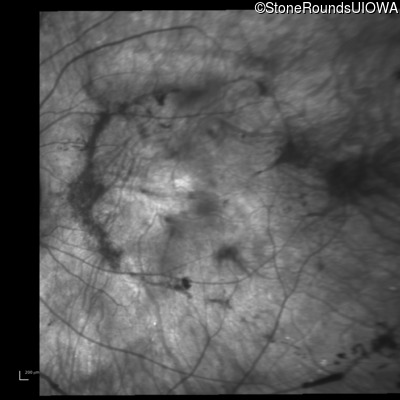

Age at visit: 38 years

OD OS

This 38 year old woman had normal vision until age 22 when she noticed poor night vision when working as a camp counselor after college. Her hearing loss was first noticed at age 3 and was correctable with hearing aids.